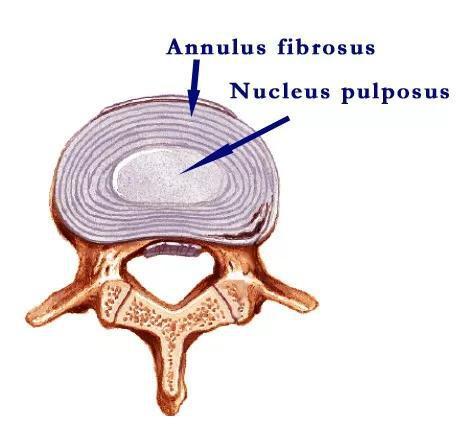

下面三个,绿色的是神经管,将发育成脑和脊髓。红色的是脊索,只在发育过程中存在,最终退化为椎间盘的髓核。左侧蓝紫色的是生心区,心脏和大血管都是从这里长出来的。

在哺乳动物里,脊椎长出后,脊索退化成椎间盘中的髓核。椎间盘突出,就是髓核突破了周围纤维环的束缚,进入椎管,压迫神经。